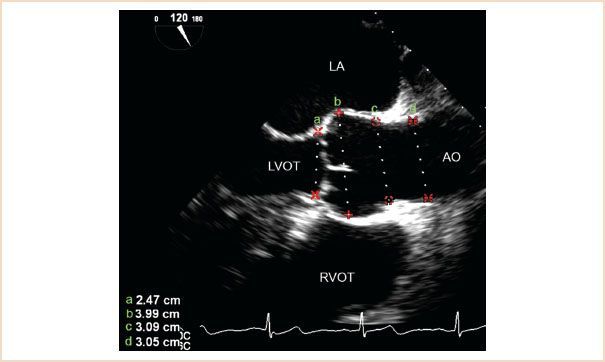

Label a, b, c, d

aortic annulus (a)

sinus of Valsalva (b)

sinotubular junction (c)

proximal ascending aorta (d)

What is a normal Aortic Annulus Size?

1.8-2.3 cm (18 - 23 mm)

What aortic valve coronary cusps are seen on the ME Aortic Valve LAX View?

Right coronary cusps is at the bottom of image (Anterior structures are more towards the bottom of the image)

NCC or LCC are at the superior aspect of the image (These are posterior structures)